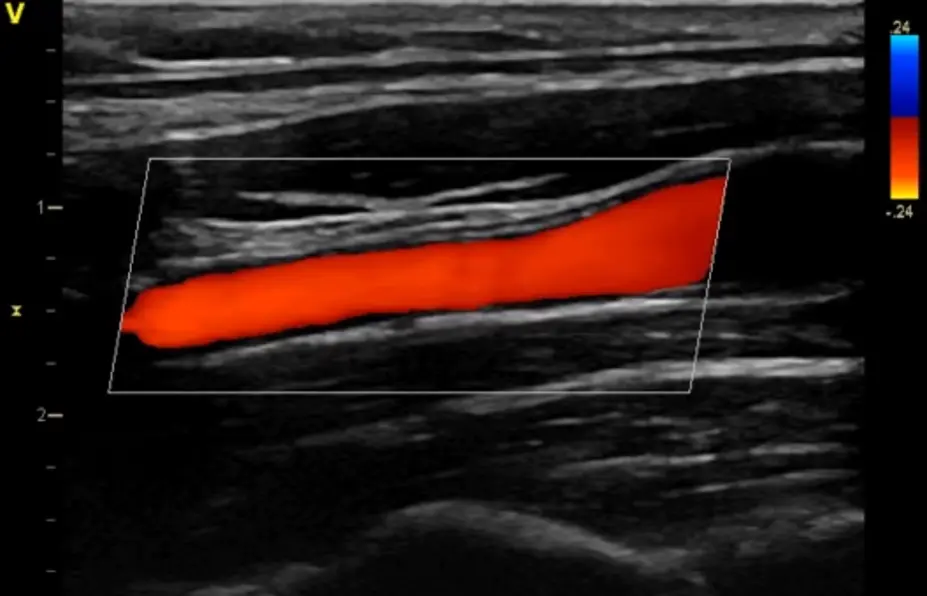

B-Flow

- Обеспечивает улучшенное пространственное и временное разрешение, помогая оценить кровоток и структуру стенок сосудов без ограничений доплеровской визуализации.

- Визуализация кровотока (BFI)

- Улучшает отображение гемодинамики с использованием инновационного алгоритма обработки сигнала.